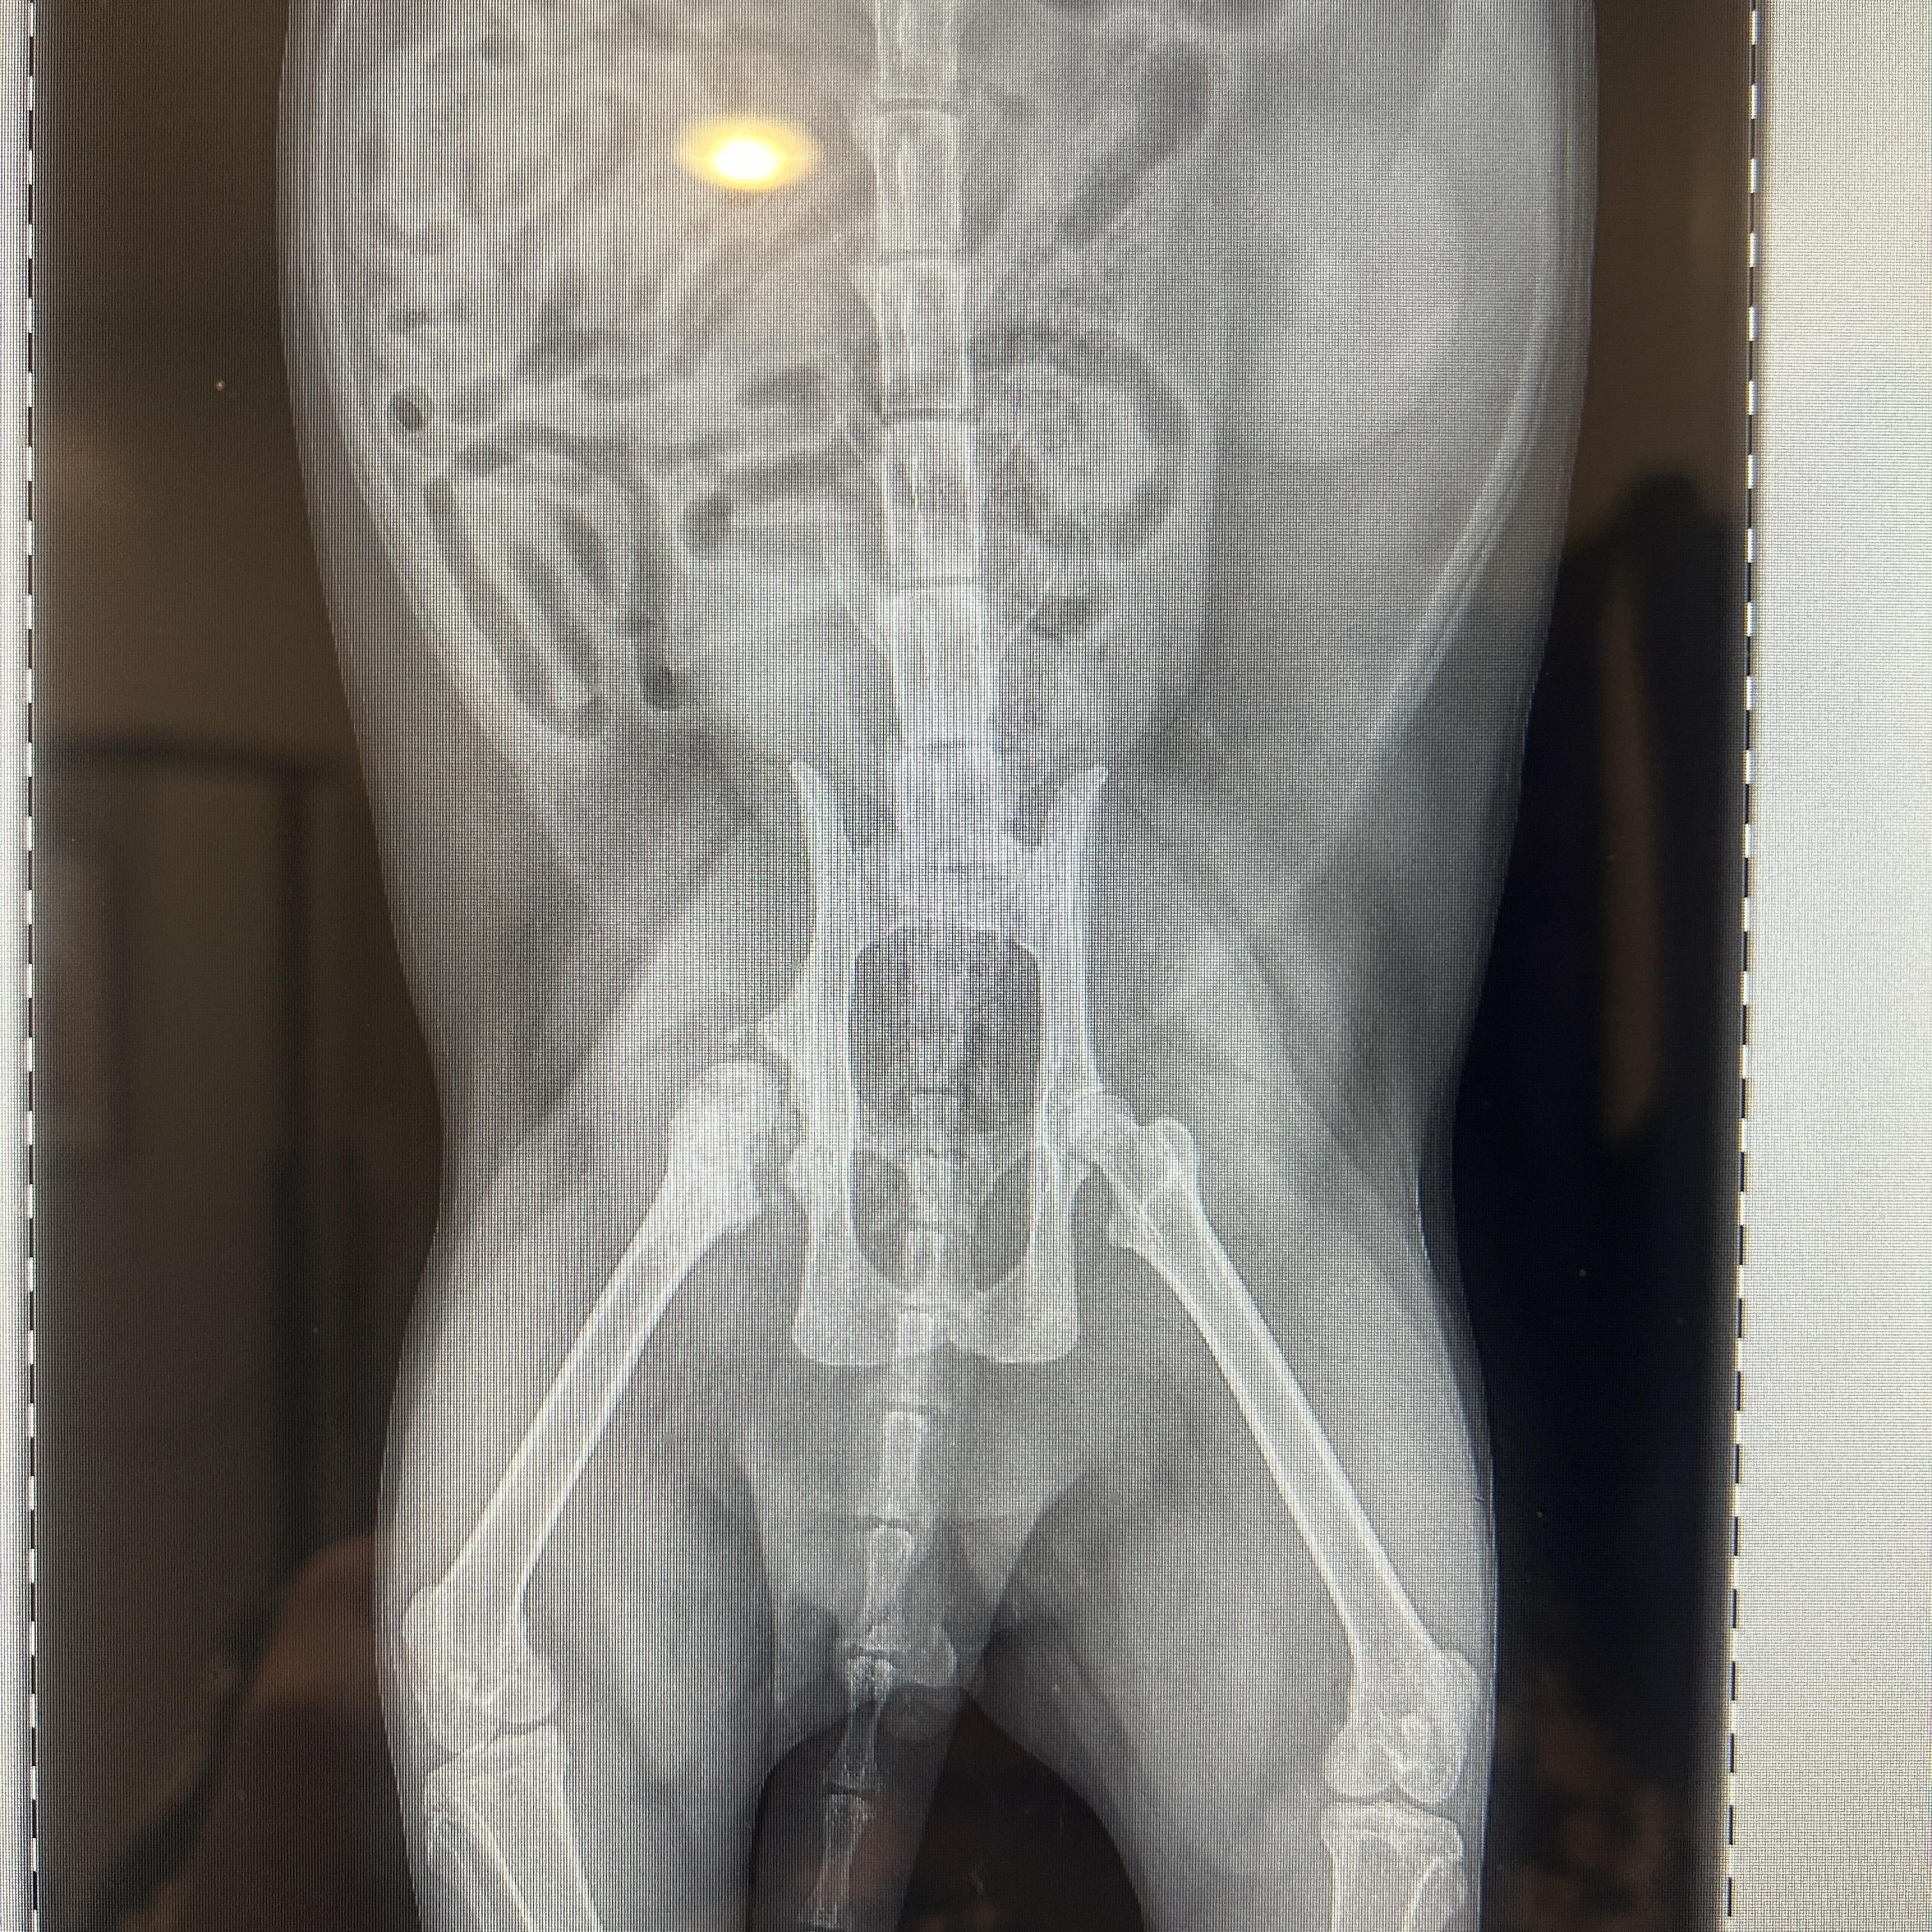

Shiromiso officially entered our program on December 9th, where I completed his full medical workup. X-rays revealed that this poor guy had suffered a severe traumatic injury at some point in his past—one that fractured his right hip and caused significant chronic changes within the joint. Interestingly, he shows no obvious lameness, which tells me the injury occurred long ago and that he adapted remarkably well. His right upper canine was also fractured, strongly suggesting he may have been struck by a vehicle.

Shiromiso officially entered our program on December 9th, where I completed his full medical workup. X-rays revealed that this poor guy had suffered a severe traumatic injury at some point in his past—one that fractured his right hip and caused significant chronic changes within the joint. Interestingly, he shows no obvious lameness, which tells me the injury occurred long ago and that he adapted remarkably well. His right upper canine was also fractured, strongly suggesting he may have been struck by a vehicle.